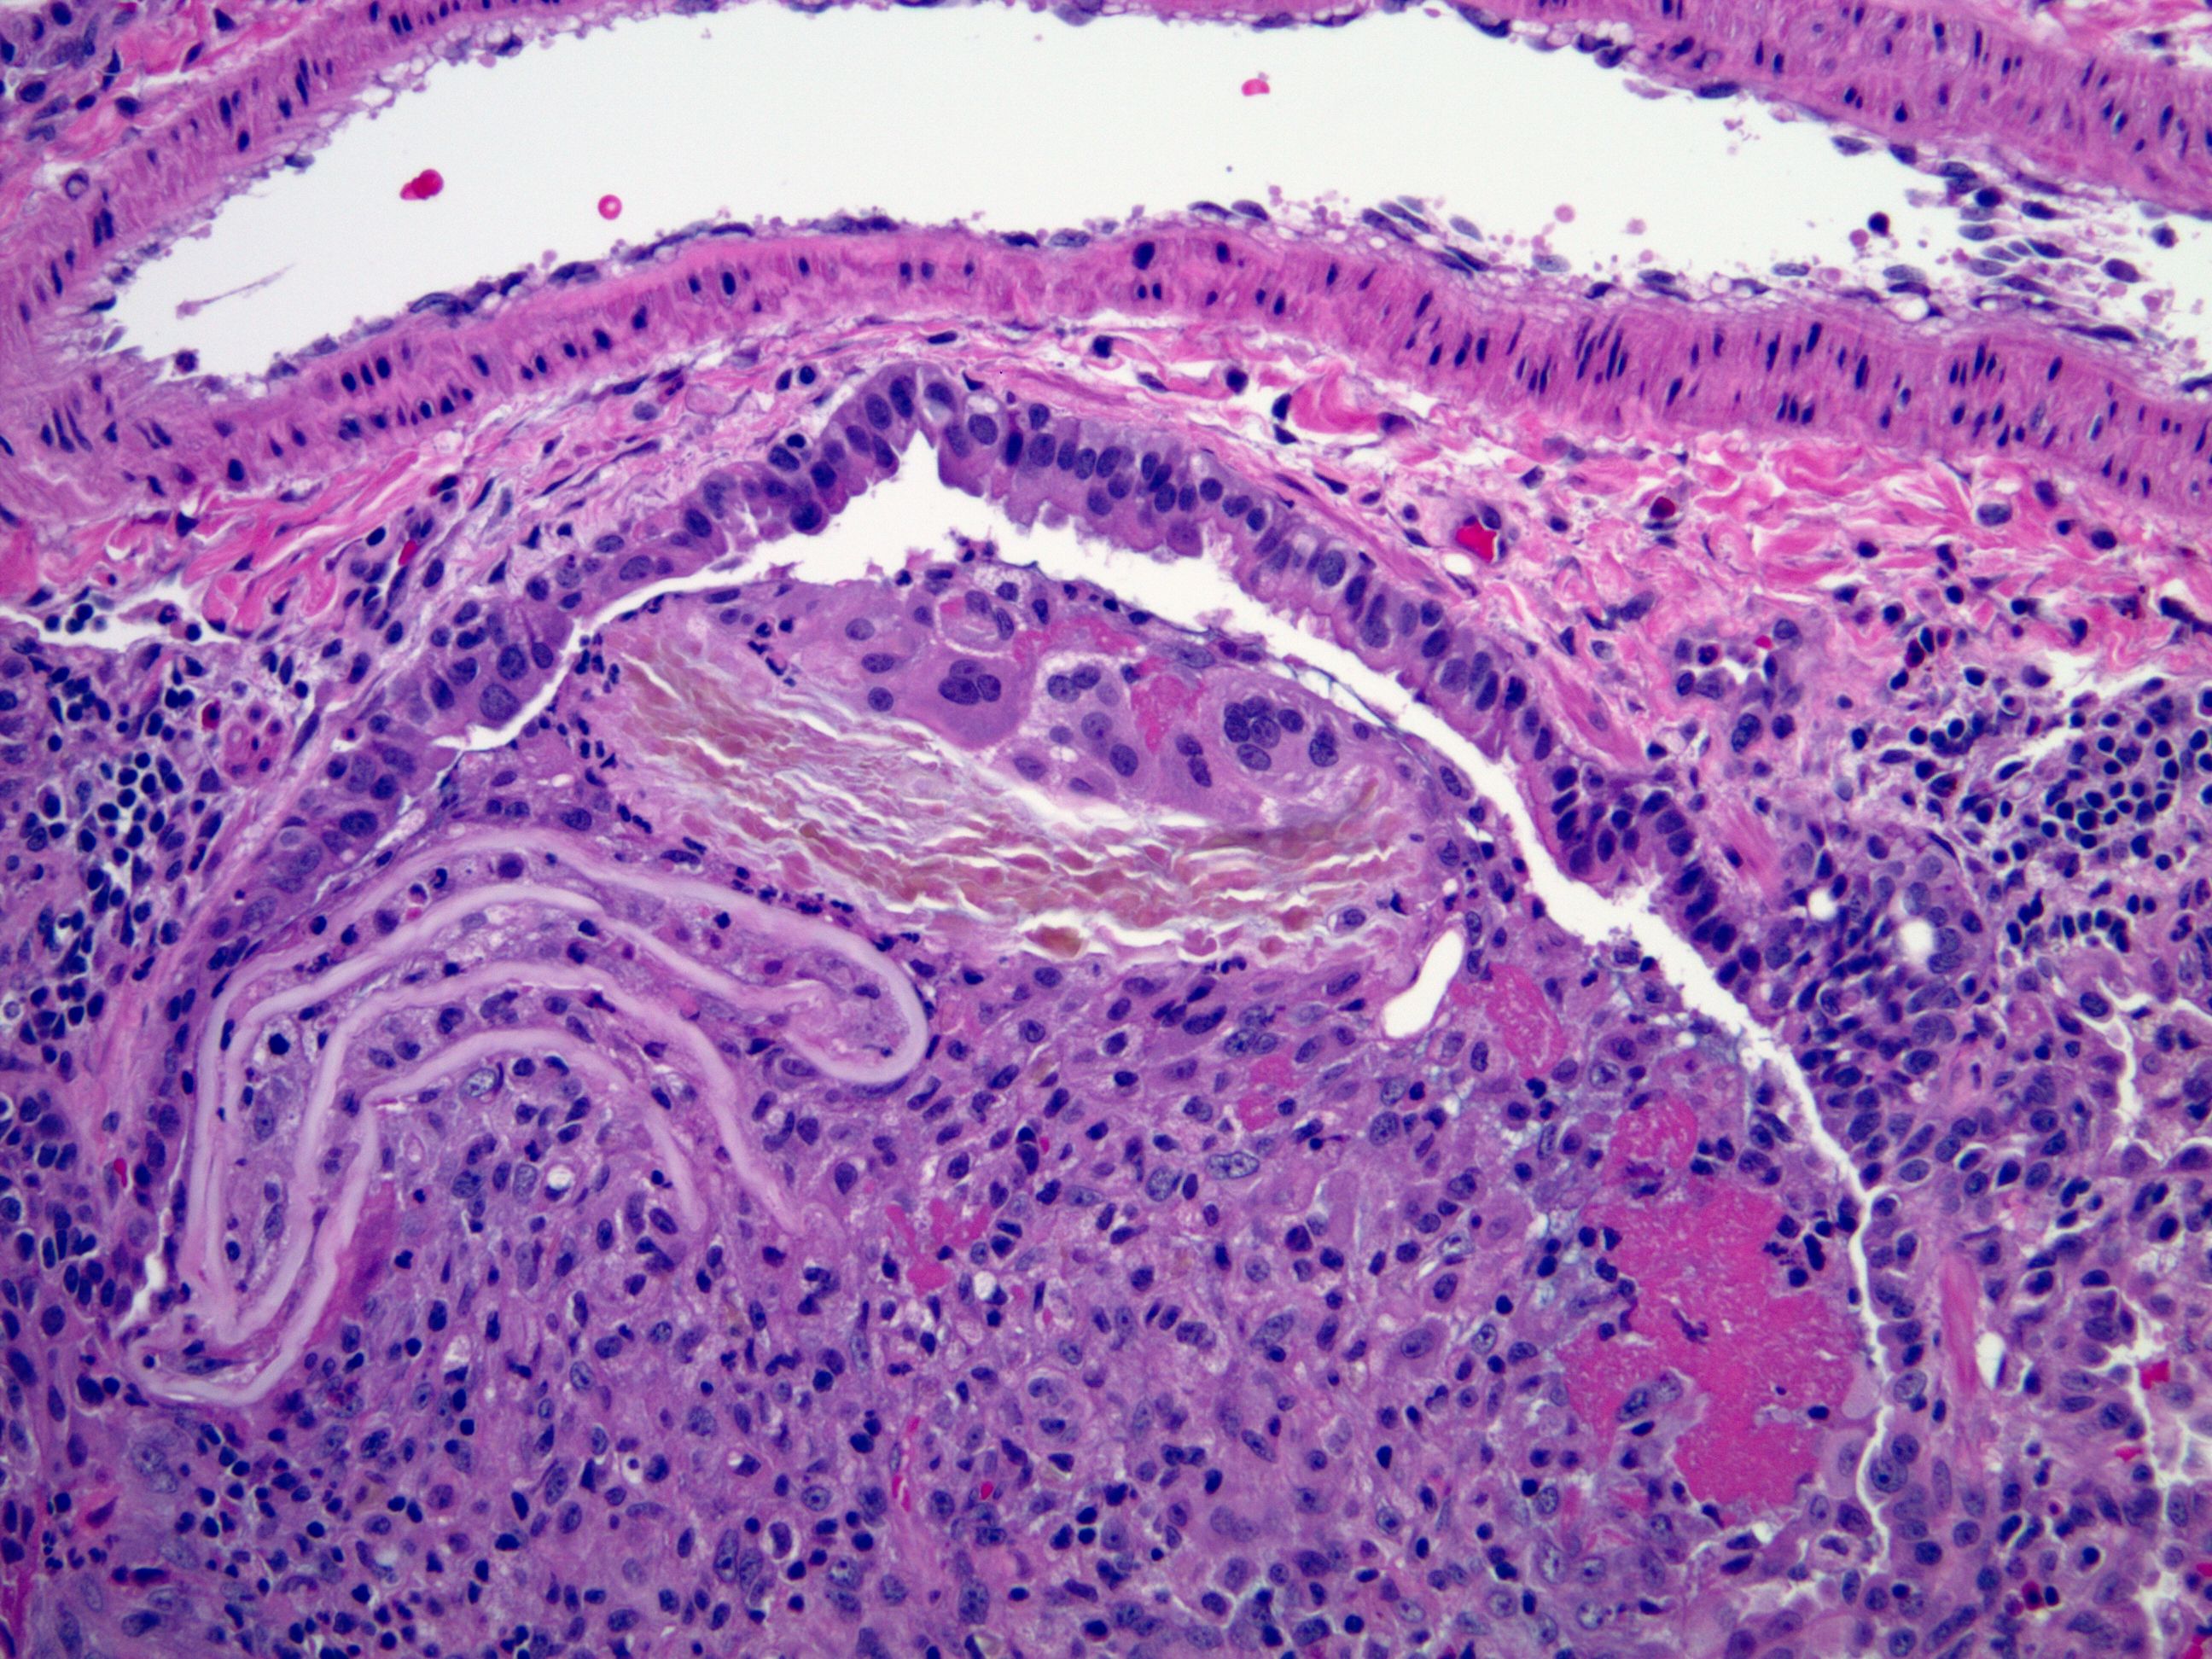

Lung histology. Aspirated food constituents corresponding to meat Does Aspirated Food Dissolve People can drown because of aspired food. If they don't then it can cause diseases, for example pneumonia. Aspiration can occur when food enters the trachea instead of the esophagus, getting stuck in your airways and triggering your body to cough. Food aspiration happens when food accidentally goes down the wrong pipe, getting into the airways instead of the digestive. Does Aspirated Food Dissolve.